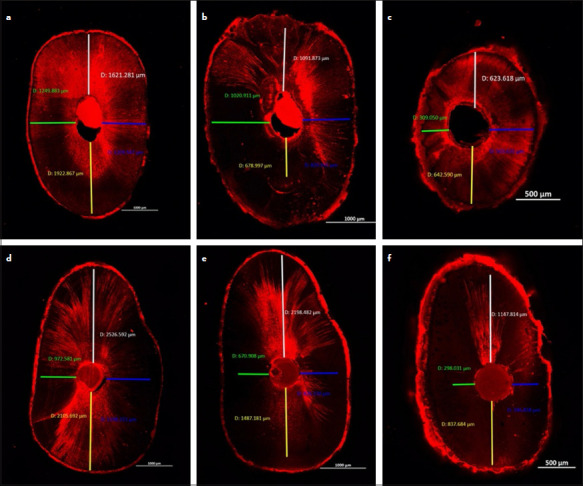

Methods: Eighteen extracted single-rooted mandibular premolars were randomly divided into two groups (n=9) according to the obturation technique used. The maximum penetration depth in microns, percentage of penetration depth, and percentage of penetration area of the NeoSEALER Flo bioceramic sealer were assessed using confocal laser scanning microscopy at different root levels; coronal, middle, and apical. Data was statistically analyzed using Kruskal-Wallis's test followed by Dunn's post hoc test with Bonferroni correction and Friedman's test followed by Nemenyi post hoc test with the significance level set at p<0.05.

Results: The single cone obturation technique has shown a statistically significantly higher percentage area of NeoSEALER Flo penetration than the lateral compaction technique at the coronal root level only. Otherwise, both obturation techniques have shown no statistically significant differences in NeoSEALER Flo penetration distance, percentage of penetration distance, and percentage of area penetration at the middle and apical root levels.